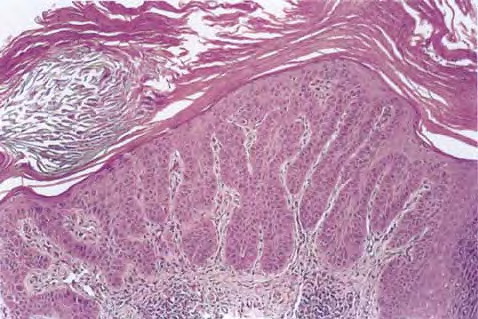

Hypertrophic actinic keratosis = التقران الضيائي الضخامي